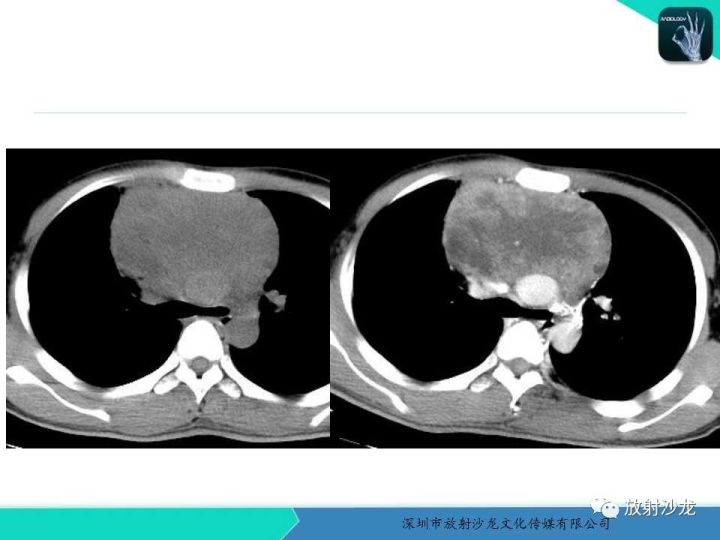

【病例】纵隔卵黄囊瘤1例CT影像表现